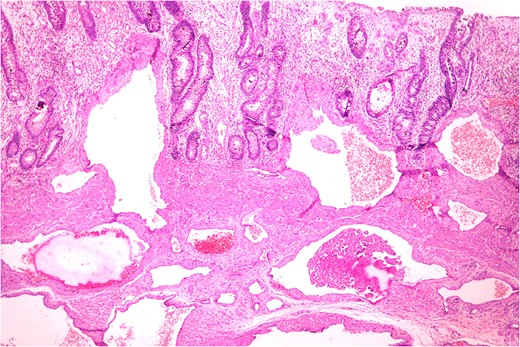

Thickened wall with tiny cystic spaces in mucosa, muscularis propria and serosa of the wall (inset: histopathological picture of the same area).

Anastomosing and dilated vascular channels in the submucosal area with congested and thrombosed blood vessels. (H&E ×400).

Histopathologically diagnosis of Cavernous Vascular Malformation—Diffuse infiltrating (expansive) type was given.